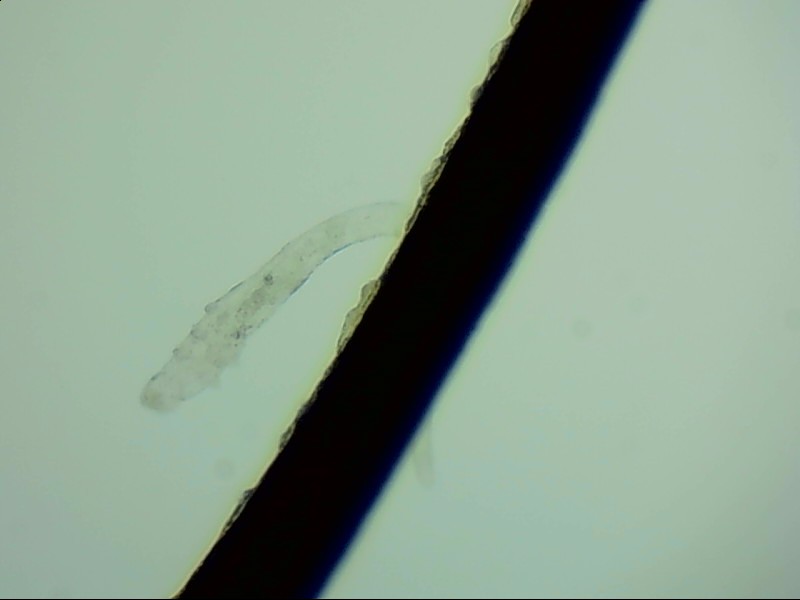

其实在人身上就寄生着两种蠕形螨,在眼部,毛囊蠕形螨寄生于睫毛毛囊,皮脂蠕形螨则分布于睫毛毛囊的皮脂腺和睑板腺内。寄生后,它们就在眼部生长、排卵、死去,完成它们的生活周期。

身体健康时,它们不会对我们造成影响,但当身体免疫力降低时,它们产的卵、排泄的废物和分泌的分泌物都会导致过敏反应,引起蠕形螨性睑缘炎,患者会因此出现眼睛发痒、眼干、有异物感、睫毛掉落等临床表现,严重者可并发结膜及角膜病变,这种病同时也是干眼症的病因之一。